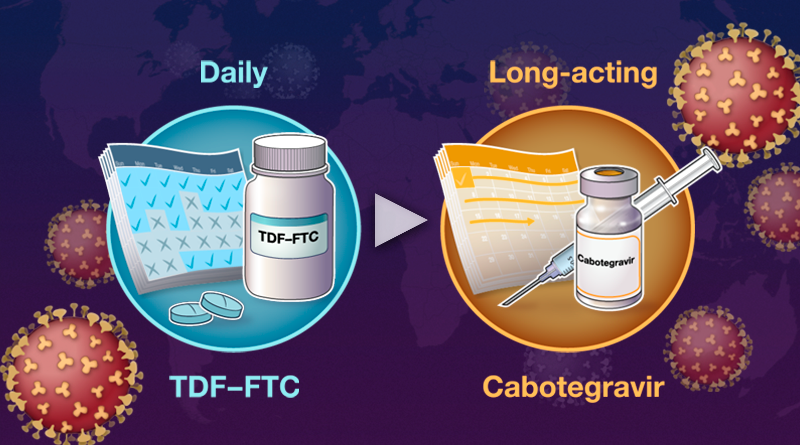

Running series of animated visual abstracts, Quick Takes, created for The New England Journal of Medicine as part of a team of illustrators, medical writers, and scientists. These short, iconographic animations aim to succinctly describe clinical trials and increase the awareness and understanding of important research findings.

Adopting The Journal’s visual style and asset library, I am responsible for the entire production process including narration editing, storyboarding, layout, illustration, and animation.